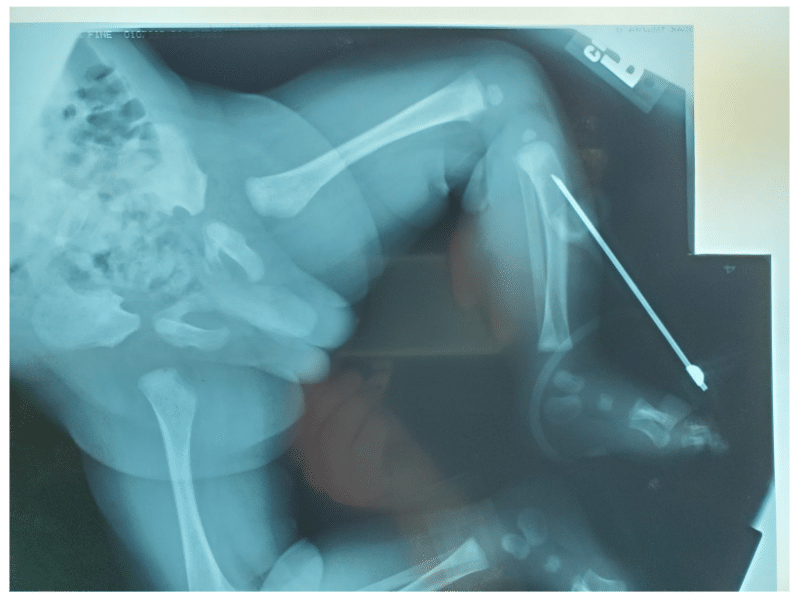

When treating a patient in cardiac arrest, the team must establish vascular access as quickly as possible. Peripheral intravenous (IV) access is the preferred route of drug administration. If the team cannot quickly start a peripheral IV, interosseous (IO) access should be attained. If neither IV nor IO access can be achieved quickly enough, the endotracheal tube (ET tube) is an acceptable route for certain resuscitation medications. More advanced vascular access procedures, such as a peripheral vein cutdown or central venous catheterization, may be considered as well.

Vascular Access

Manual IO Insertion from 25 Years Ago

Contemporary IO Placement